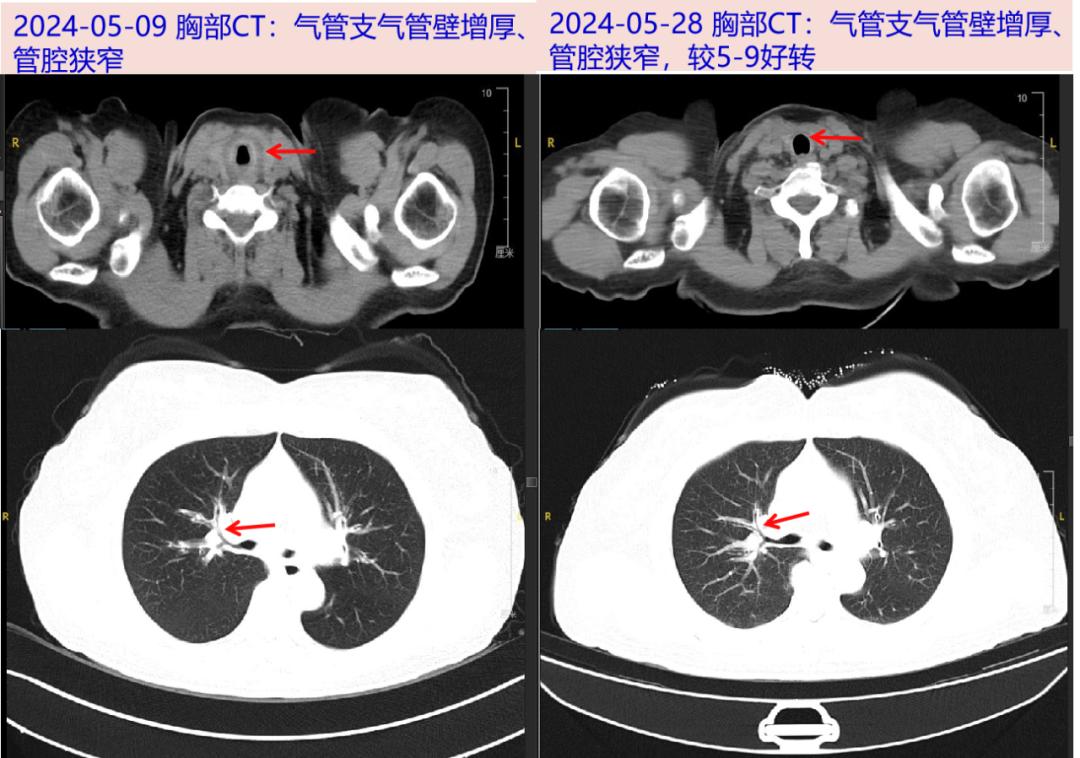

出院后随访2024-05-29 感染病科门诊随访:体温平,无咳嗽、咳痰,复查CRP 5.1mg/L,ESR 8mm/H,PCT 0.03ng/ml;胸部CT:气管壁稍增厚,较前稍好转。

患者中年女性,慢性起病;主要表现为发热、咳嗽、咳痰,伴有气促等非特异性症状;CRP、ESR明显升高,铁蛋白升高,自身抗体阴性、病原学检测阴性,胸部CT:支气管壁增厚;支气管镜下可见气管及叶、段支气管壁粘膜肿胀,病理活检未见恶性细胞。PET/CT示累及全身多处软骨(气管、甲状软骨、环状软骨、双侧多处肋软骨)可能;糖皮质激素治疗后体温平,咳嗽咳痰气促好转,炎症标志物下降;故诊断成立。

RP累及气道时,CT影像表现为气道壁增厚、钙化,气道软化、狭窄等;气管镜下见气道黏膜肿胀、软骨环消失等征象,导致气管狭窄、塌陷等。但上述征象均无特异性。而PET/CT对于软骨炎有独特的FDG摄取表现,故在早期诊断中具有重要意义,还可判断疾病活动度和累及范围,如对高代谢灶进行活检可提高阳性检出率。本例患者胸部CT影像及气管病理为非典型RP,但PET/CT多部位软骨FDG摄取增高符合典型软骨炎症表现,进一步协助RP诊断。此外,血沉、CRP在本病活动期可明显升高。本例患者表现为血沉增快(80mm/h),CRP大于100mg/L,而毒血症状不重,抗感染治疗无效,此时需注意排查风湿免疫系统疾病。血沉及CRP在风湿免疫系统疾病中不仅会随病情的恶化或好转而升高或降低,且与疾病的严重程度、预后密切相关,也是达标治疗的重要指标。中山感染病科已诊断此病近10例,本病虽不是感染病,但容易误诊为呼吸道感染,给予抗感染治疗。感染病科医生必须学习此疾病,避免误诊及滥用抗生素。如误诊可导致管腔狭窄及塌陷,不利于疾病的恢复,可导致患者反复发生肺炎。